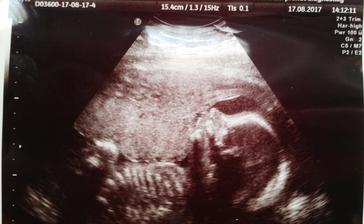

22.6.2017 kontrolní ultrazvuk. Jsi v pořádku, mávalas mi ručičkama a hopsala 🙂